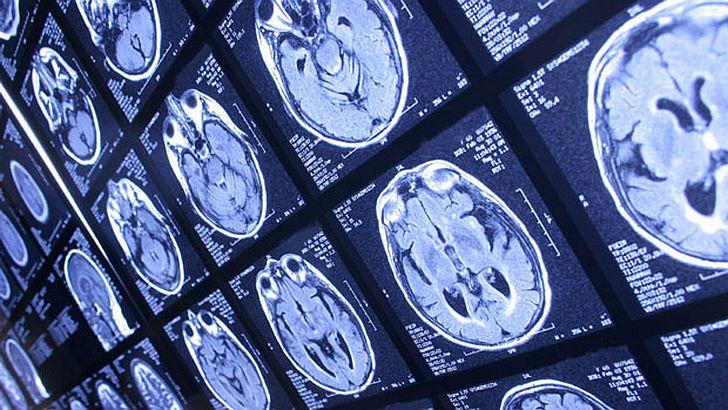

Pornind de la articolul publicat de Dr. Crabtree, un grup de cercetători de la Harvard a descoperit că unul din elementele care duce la scăderea IQ-ului populaţiei este chiar fluorul, substanţa care este folosită frecvent în apa pe care o consumăm de la robinet.

"Fluorul care se găseşte în apă are efecte adverse în dezvoltarea cerebrală a copiilor", spuneau cercetătorii în articolul publicat în revista de specialitate Environmental Health Perspectives.

Acesta este cel de-al 24-lea studiu care are acelaşi rezultat privind efectele pe care flourul din apă le are asupra IQ-ului copiilor.

Mai mult, revista Proceedings of the National Academy of Sciences a publicat un articol potrivit căruia pesticidele, care se găsesc peste tot în fructele şi legumele pe care le cumpărăm din comerţ, produc schimbări dramatice în structura creierului, iar cel mai şocant este scăderea inteligenţei populaţiei consumatoare de alimente astfel infestate.

Nu în ultimul rând, un studiu amplu, realizat pe 14.000 de copii arată legătura care există între alimentele procesate şi scăderea IQ-ului. Rezultatele acestui studiu, publicate în revista Natural Society, sunt de-a dreptul îngrijorătoare: dacă un copil începe să consume hrană procesată organic de la vârsta de 3 ani, în următorii cinci ani se va observa declinul IQ-ului său.